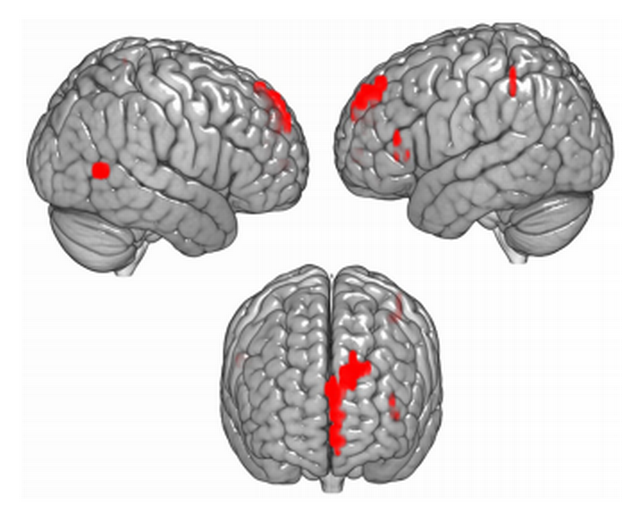

Problemas como depressão, ansiedade e estresse pós-traumático estão correlacionados com alterações cerebrais. Apesar disso, exames capazes de criar imagens mapeando esse tipo de alteração não costumam ser utilizados pela psiquiatria em diagnósticos. Exames de imagem por ressonância magnética funcional, por exemplo, são capazes de coletar imagens do cérebro que indicam quais áreas são mais irrigadas por sangue oxigenado quando a pessoa examinada recebe diversos estímulos. Eles são, no entanto, normalmente utilizados para identificar alterações como tumores, ou o impacto de derrames cerebrais e doenças como Alzheimer. Um dos motivos pelos quais o mesmo tipo de técnica não é aplicado em diagnósticos psiquiátricos é porque as alterações no cérebro não são tão drásticas e claras. Há grandes diferenças, mesmo entre pessoas com o mesmo tipo de transtorno, e é difícil aprender a identificar a olho nu as nuances entre o cérebro de alguém saudável e alguém com problemas psiquiátricos. Em um estudo publicado em outubro de 2017 na revista Nature Human Behaviour, pesquisadores ligados a universidades americanas afirmam, no entanto, que foram capazes de usar aprendizado de máquina (ou “machine learning”) para detectar em imagens cerebrais sinais sutis que diferenciam pessoas com “ideações suicidas” – ou seja, que pensam em cometer suicídio – e pessoas sem essas ideações. Intitulado “Aprendizado de máquina de representações neurais de suicídio e conceitos emocionais identifica jovens suicidas”, o trabalho aponta que a técnica pode vir a viabilizar o uso da ressonância em diagnósticos psiquiátricos. No aprendizado de máquina, os próprios algoritmos se desenvolvem de forma relativamente independente. No caso, os pesquisadores usaram a técnica para que o algoritmo “se ensinasse” a ler e identificar padrões nos exames. O trabalho afirma que o algoritmo se mostrou capaz de identificar a imagem do cérebro de uma pessoa com ideação suicida com uma precisão de 91%. E que atingiu precisão de 94% em diferenciar pessoas com ideação suicida que tinham tentado se suicidar e pessoas com o mesmo tipo de pensamentos, mas que não tinham tentado se suicidar. Apesar de o grupo estudado ser pequeno, a pesquisa afirma que o nível alto de acertos atingido pelo algoritmo ao classificar as pessoas, de mais de 90%, “indica que o tamanho da amostra foi suficiente”. O trabalho afirma que ainda é preciso verificar se o mesmo nível de acerto ocorreria ao discriminar pessoas com ideação suicida de outros grupos com problemas psiquiátricos em geral, mas que os bons resultados em distinguir quem tentou e não tentou suicídio é um sinal de que isso é possível. “Dentro de suas limitações, o estudo atual é um primeiro passo no sentido de detectar um transtorno psiquiátrico da mente e do cérebro.”

Problemas como depressão, ansiedade e estresse pós-traumático estão correlacionados com alterações cerebrais. Apesar disso, exames capazes de criar imagens mapeando esse tipo de alteração não costumam ser utilizados pela psiquiatria em diagnósticos. Exames de imagem por ressonância magnética funcional, por exemplo, são capazes de coletar imagens do cérebro que indicam quais áreas são mais irrigadas por sangue oxigenado quando a pessoa examinada recebe diversos estímulos. Eles são, no entanto, normalmente utilizados para identificar alterações como tumores, ou o impacto de derrames cerebrais e doenças como Alzheimer. Um dos motivos pelos quais o mesmo tipo de técnica não é aplicado em diagnósticos psiquiátricos é porque as alterações no cérebro não são tão drásticas e claras. Há grandes diferenças, mesmo entre pessoas com o mesmo tipo de transtorno, e é difícil aprender a identificar a olho nu as nuances entre o cérebro de alguém saudável e alguém com problemas psiquiátricos. Em um estudo publicado em outubro de 2017 na revista Nature Human Behaviour, pesquisadores ligados a universidades americanas afirmam, no entanto, que foram capazes de usar aprendizado de máquina (ou “machine learning”) para detectar em imagens cerebrais sinais sutis que diferenciam pessoas com “ideações suicidas” – ou seja, que pensam em cometer suicídio – e pessoas sem essas ideações. Intitulado “Aprendizado de máquina de representações neurais de suicídio e conceitos emocionais identifica jovens suicidas”, o trabalho aponta que a técnica pode vir a viabilizar o uso da ressonância em diagnósticos psiquiátricos. No aprendizado de máquina, os próprios algoritmos se desenvolvem de forma relativamente independente. No caso, os pesquisadores usaram a técnica para que o algoritmo “se ensinasse” a ler e identificar padrões nos exames. O trabalho afirma que o algoritmo se mostrou capaz de identificar a imagem do cérebro de uma pessoa com ideação suicida com uma precisão de 91%. E que atingiu precisão de 94% em diferenciar pessoas com ideação suicida que tinham tentado se suicidar e pessoas com o mesmo tipo de pensamentos, mas que não tinham tentado se suicidar. Apesar de o grupo estudado ser pequeno, a pesquisa afirma que o nível alto de acertos atingido pelo algoritmo ao classificar as pessoas, de mais de 90%, “indica que o tamanho da amostra foi suficiente”. O trabalho afirma que ainda é preciso verificar se o mesmo nível de acerto ocorreria ao discriminar pessoas com ideação suicida de outros grupos com problemas psiquiátricos em geral, mas que os bons resultados em distinguir quem tentou e não tentou suicídio é um sinal de que isso é possível. “Dentro de suas limitações, o estudo atual é um primeiro passo no sentido de detectar um transtorno psiquiátrico da mente e do cérebro.”